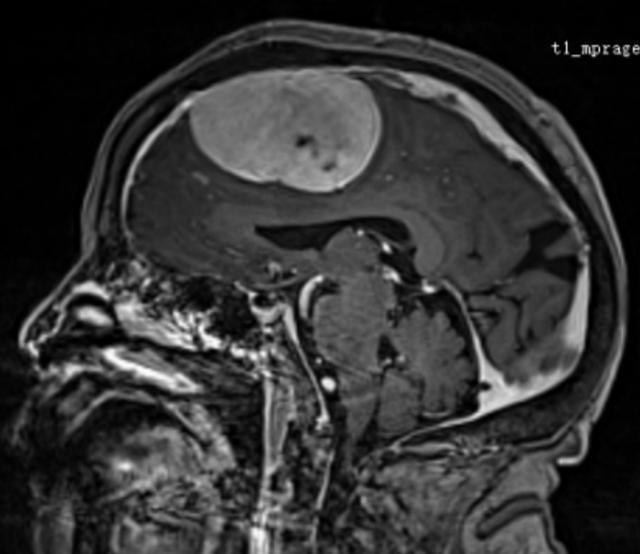

(▲患者颅内肿瘤影像)

时间回溯到年前,李奶奶被查出颅内肿瘤,且肿瘤已侵犯矢状窦、颅骨及头皮。由于年事已高,又身患多种慢性病,家属带着她辗转北京、上海多家医院求医,却均因手术风险过高被婉拒——多家医院认为,老人高龄叠加多重基础病,且长期使用抗凝药物,手术及麻醉过程中随时可能出现致命并发症,手术难度与风险远超常规。

一个月前,李奶奶病情突然恶化,出现严重食欲减退、意识模糊等症状,家属抱着最后一丝希望,将她送到湖南省第二人民医院(省脑科医院)脑血管神经外科就诊。入院检查显示,老人右额窦旁的巨大脑膜瘤已严重挤压脑组织,生命体征极不稳定。